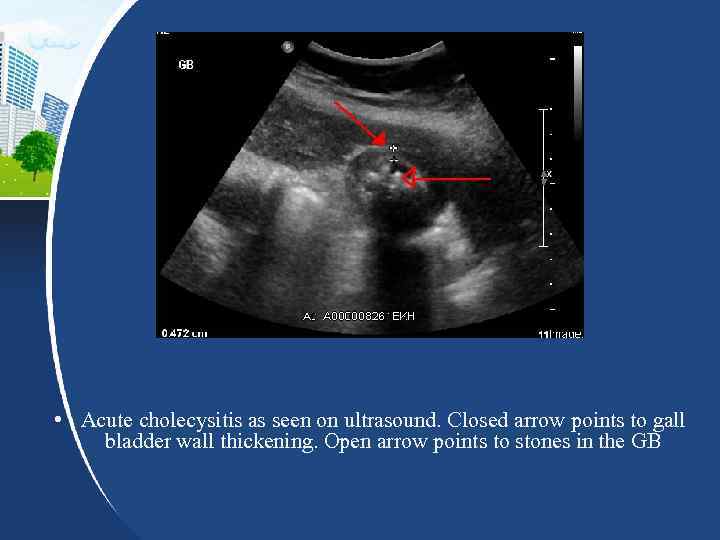

• Acute cholecysitis as seen on ultrasound. Closed arrow points to gall bladder wall thickening. Open arrow points to stones in the GB

Diagnosis • • Cholecystitis is usually diagnosed by a history of the above symptoms, as well as examination findings: Fever (usually low grade in uncomplicated cases) Tender right upper quadrant with or without Murphy's sign Ortner's sign — tenderness when hand taps the edge of right costal arch Georgievskiy — Myussi's sign (phrenic nerve sign) — pain when press between edges of sternocleidomastoid Boas' sign — Increased sensitivity below the right scapula (also due to phrenic nerve irritation) Subsequent laboratory and imaging tests are used to confirm the diagnosis and exclude other possible causes. Ultrasound is paramount in differential diagnosis. Ultrasound findings suggestive of acute cholecystitis include pericholecystic fluid, >4 mm gallbladder wall thickening, and Murphy's sign. Visualization of gallstones on ultrasound helps confirm the diagnosis of cholecystitis. Computed Tomography (CT) scan, Magnetic Resonance Imaging (MRI), and Hepatobiliary Scintigraphy (HBS) are also useful in the detection of cholecystitis. Endoscopic Retrograde Cholangiopancreatography (ERCP) may be useful to visualize the anatomy.